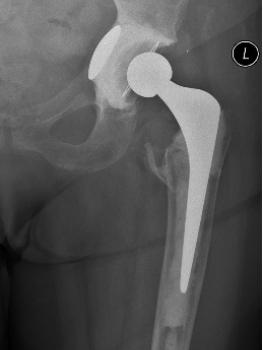

Figure 11 & Figure 12: Cemented fixation in poor bone has the immediate advantage of full weight-bearing in frail patients, especially after trauma.